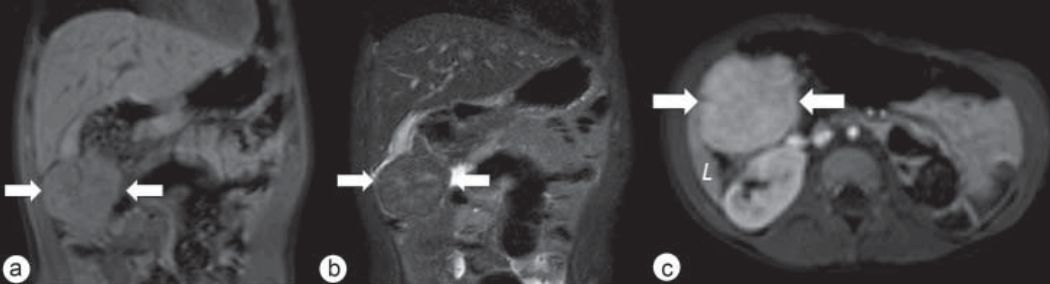

主体位于肝外:女,31 岁,FNH 病变主体位于肝右叶下方,与肝右叶相连,可见粗大肝静脉引流 医学百科网 | YxBaike.Com

医学百科网 | YxBaike.Com